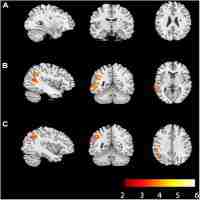

Microstructural differences in the aging white matter of APOE allele ε 4 carriers : a diffusional kurtosis imaging and diffusion tensor imaging study

| Abstract | tensor imaging study Jean-Philippe Coutu, H. Diana Rosas, and David H. Salat MGH/MIT/HMS Athinoula A. Martinos Center for Biomedical Imaging, Charlestown, Massachusetts, United States, Health Sciences and Technology, MIT/Harvard, Cambridge, Massachusetts, United States, Neurology, MGH, Harvard Medical School, Boston, Massachusetts, United States, Radiology, MGH, Harvard Medical School, Boston, Massachusetts, United States |